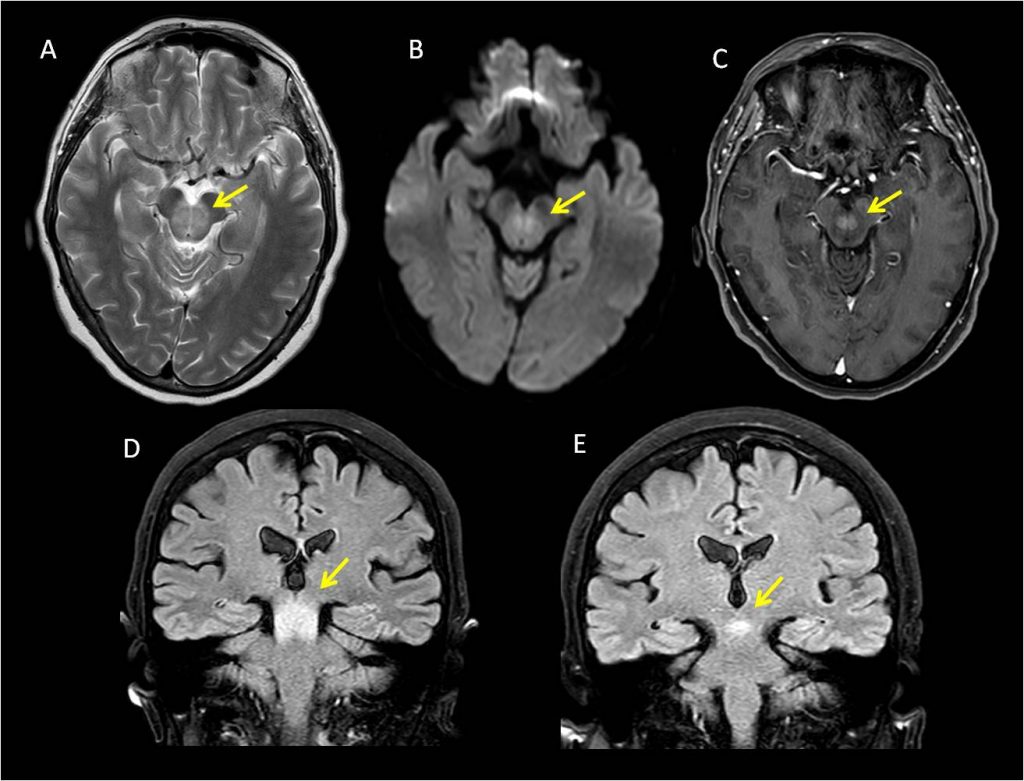

A. TSE T2 transversal

B. B1000 transversal

C. T1 EG 3D con supresión grasa tras administración de gadolinio iv.

D. FLAIR coronal

E. FLAIR coronal tras un mes de tratamiento

Área de hiperintensidad en secuencias T2/FLAIR de la vertiente central del mesencéfalo que preserva la arquitectura del mismo, con una zona central que restringe la difusión y realza tras la administración de contraste a nivel del brachium conjunctivum. El control al mes tras tratamiento específico muestra una reducción muy significativa de la alteración de señal a nivel mesencefálico.